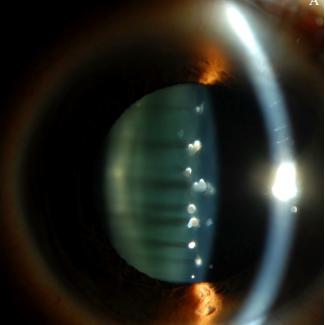

这名患者明确自己之前没有眼部疾病或糖尿病等系统疾病史,而检查发现,患者的双眼晶状体前囊下平行排列的点阵状白色混浊,右眼比左眼更为明显,可见其前皮质下点状混浊,但尚未累及晶状体核及后皮质,其他检查正常。

双眼点阵状晶体混浊,患者右眼检查结果